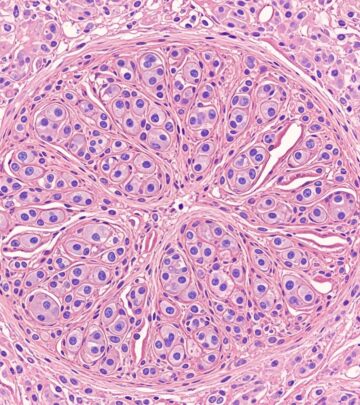

- Tzanck smear: Multinucleated giant cells (less specific).